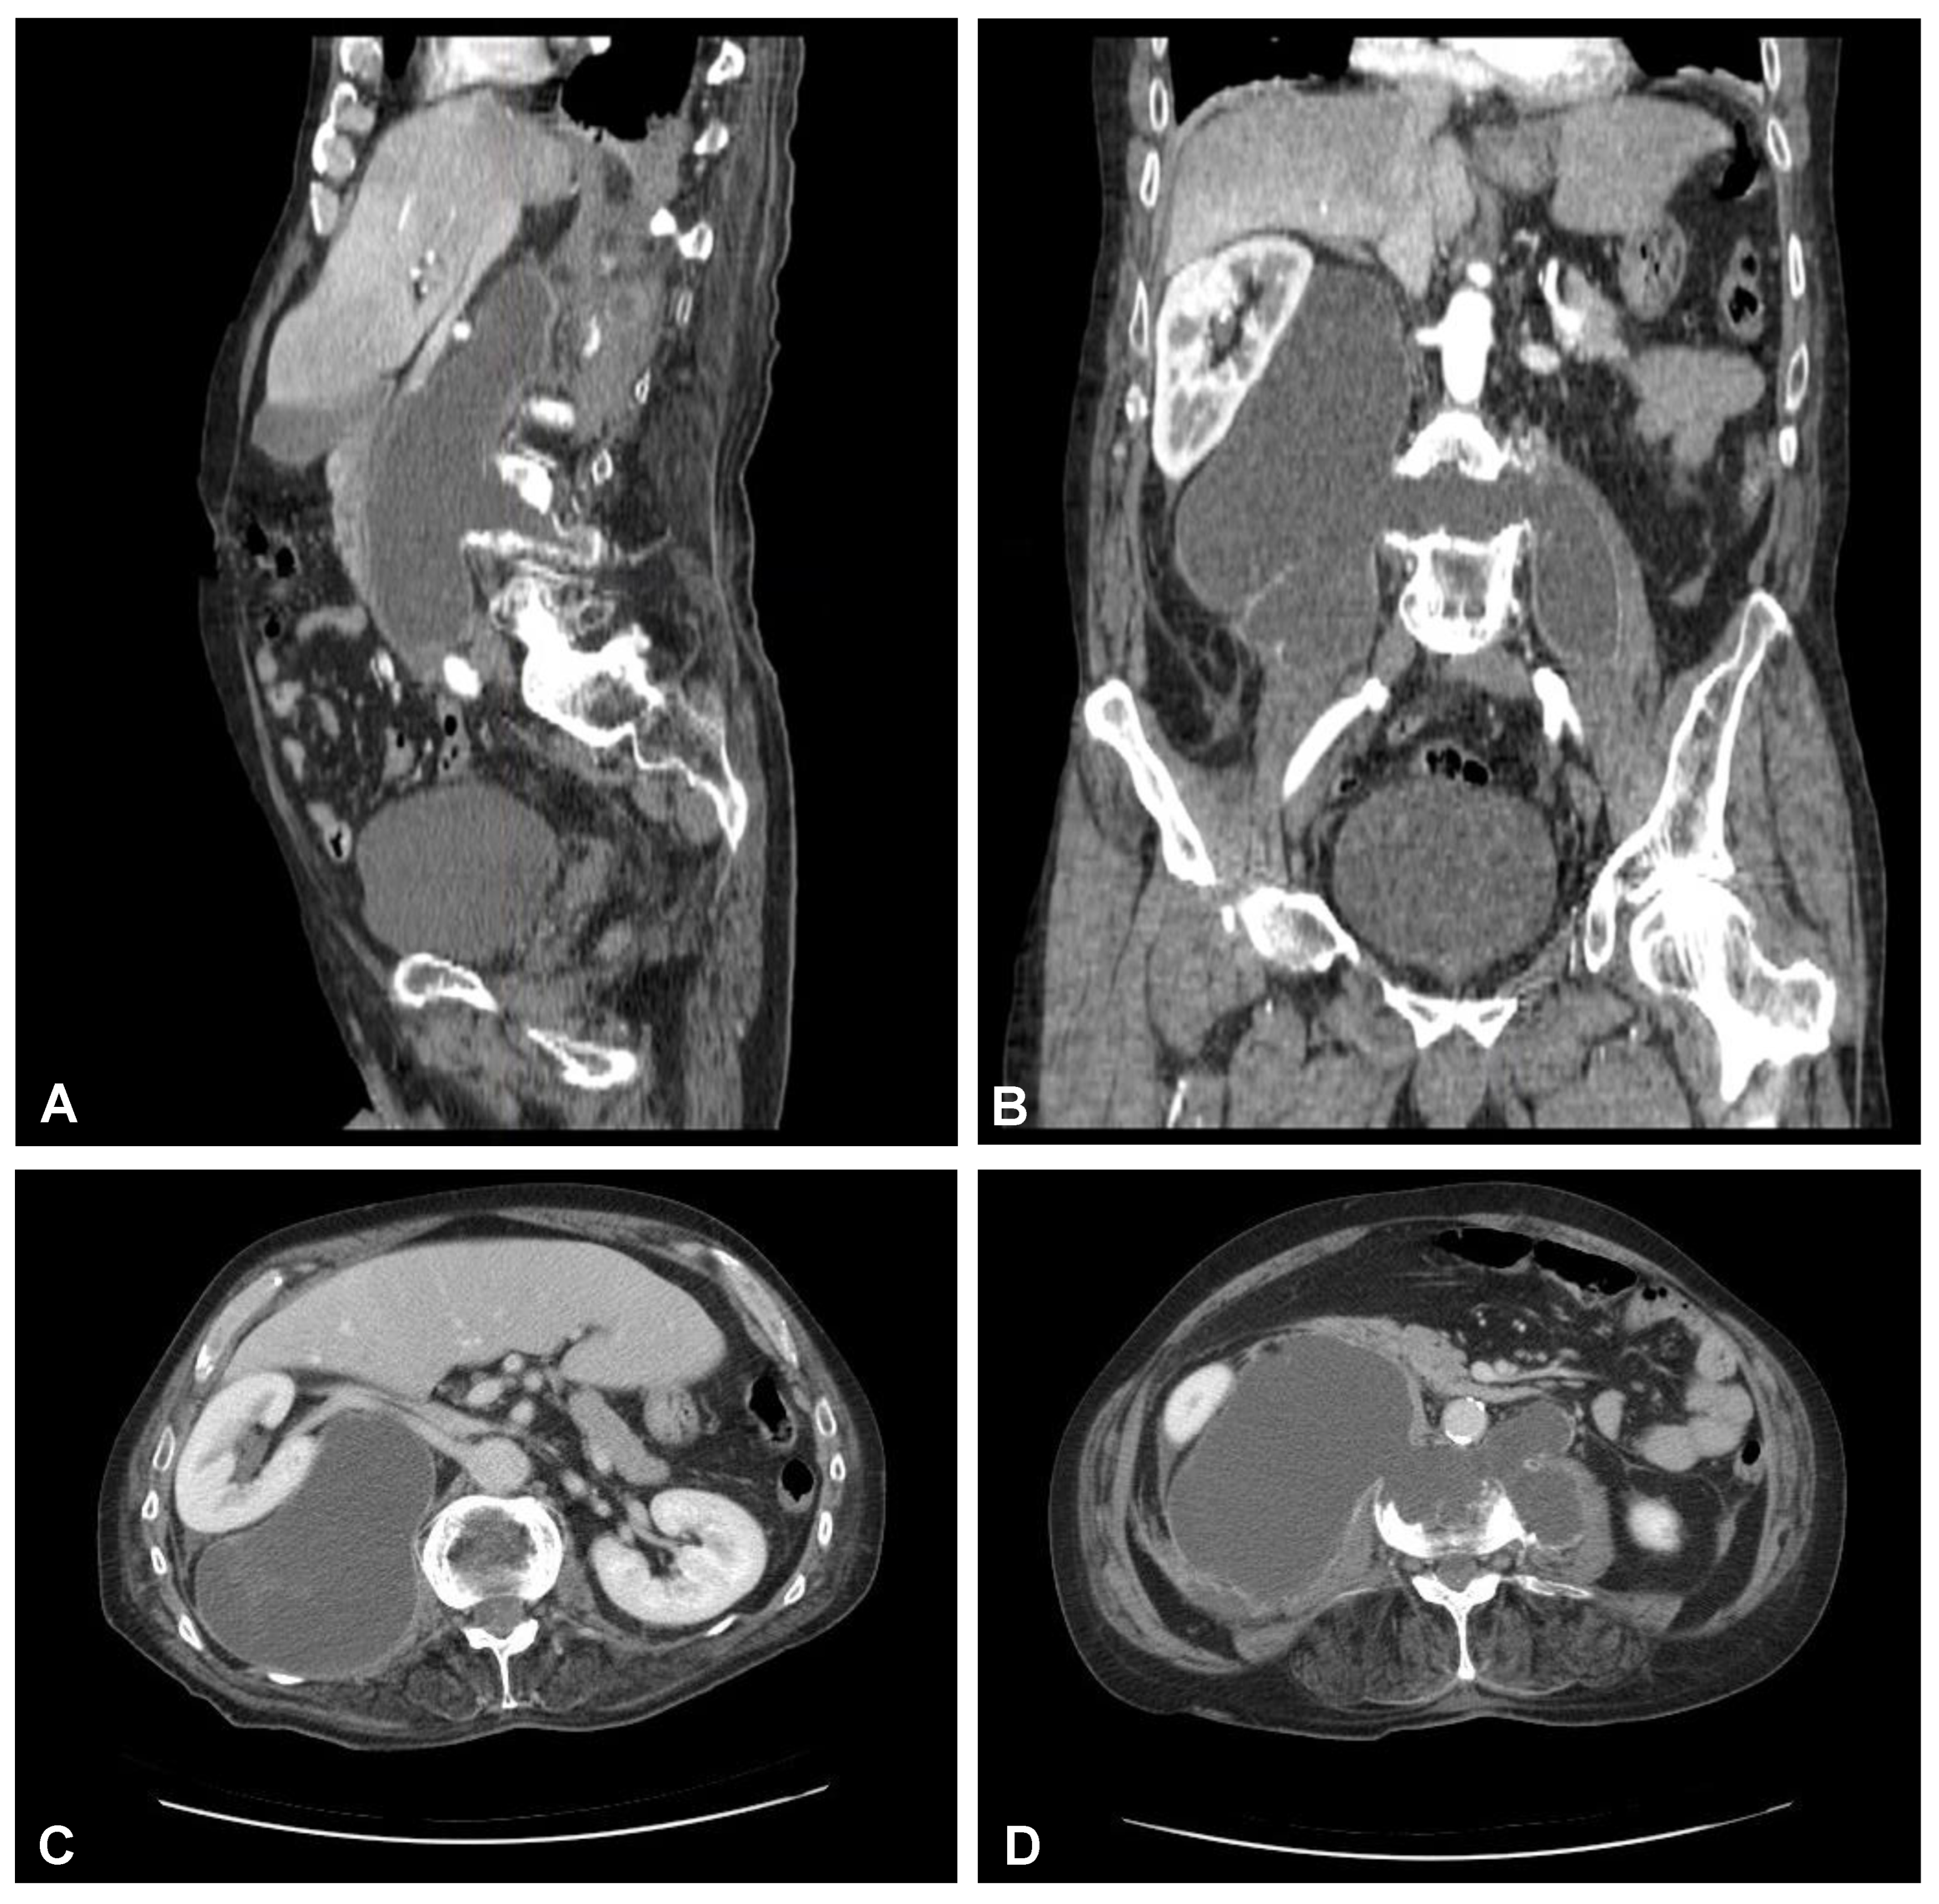

A 59-year-old man presented to the hospital with atypical abdominal pain for a few days, three weeks after sustaining a low-energy fall. At the time of admission, the patient had normal upper and lower extremity strength and no pathologic reflexes, as well as no bowel or bladder incontinence. The initial performed plain radiograph of the abdomen demonstrated a fracture line completely slicing through the L3/L4 intervertebral disc space and features of ASH (Figure 1). The additional performed computed tomography (CT) scans demonstrated a three-column fracture of L4 vertebrae with a suspicious transdiscal injury at the L3/L4 level, which was morphologically classified as type B3/C according to the Arbeitsgemeinschaft für Osteosynthesefragen (AO) spine classification. Moreover, at the fracture level, the hypodense area communicating intervertebral disc space with both psoas major muscles forming a massive, well-defined fluid-like collection in the right retroperitoneum was observed (Figure 2). In addition, contrast-enhanced CT (CE-CT) showed a thick enhancing wall and internal septae within an area measuring a total of 10 cm × 20 cm × 10 cm (TR × AP × CC) (Figure 3). Furthermore, the performed magnetic resonance imaging (MRI) scans confirmed the cystic nature of the lesion, which had no specific characteristics and demonstrated intensities that were similar to those of cerebrospinal fluid (CSF) (Figure 4). Taking into consideration the history and radiological features, suspicion of spondylodiscitis with osteomyelitis features and retroperitoneal abscess formation was provided by the radiologist. Blood analysis performed on admission revealed the following results: hemoglobin (Hb): 9.6 g/dL; platelet (PLT): 192 × 109/L; white blood cell (WBC): 9.7 × 109/L; and creatinine (CREA): 0.42 mg/dL. Despite the lack of infection symptoms, the patient was empirically administered intravenous antibiotics, including meropenem (1 g every 8 h) and vanomycin (1 g every 12 h), without waiting for microbiological confirmation.

Figure 2. Preoperative sagittal (AC) and axial (D,E) CT scans (non-contrast enhanced) of the lumbar spine demonstrating hypodense area at the L3/L4 intervertebral disc space communicating with both psoas major muscles forming massive well-defined fluid-like collection in the right retroperitoneum.